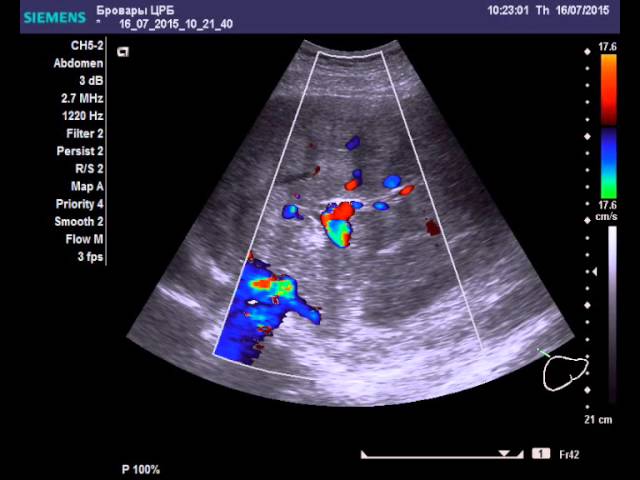

Внешние признаки рака печени требуют подтверждения диагноза с помощью УЗИ с ЦДК, цветным допплеровским картированием. На экране во время процедуры определяется:

- видоизмененное состояние органа, при болезни нижний край закругляется;

- неоднородная структура, повышенная плотность паренхимы, функционально-активные эпителиальные клетки;

- узлы в зоне ветвей воротной вены;

- уплотнение сосудов на поверхности органа;

- увеличенный размер;

- наличие гиперэхогенных узлов.

В основном такая раковая опухоль проявляется на сканировании в смешанной форме. Участки органа по структуре становятся неоднородными: в одном месте структура уплотняется, в другом истончается из-за некроза.